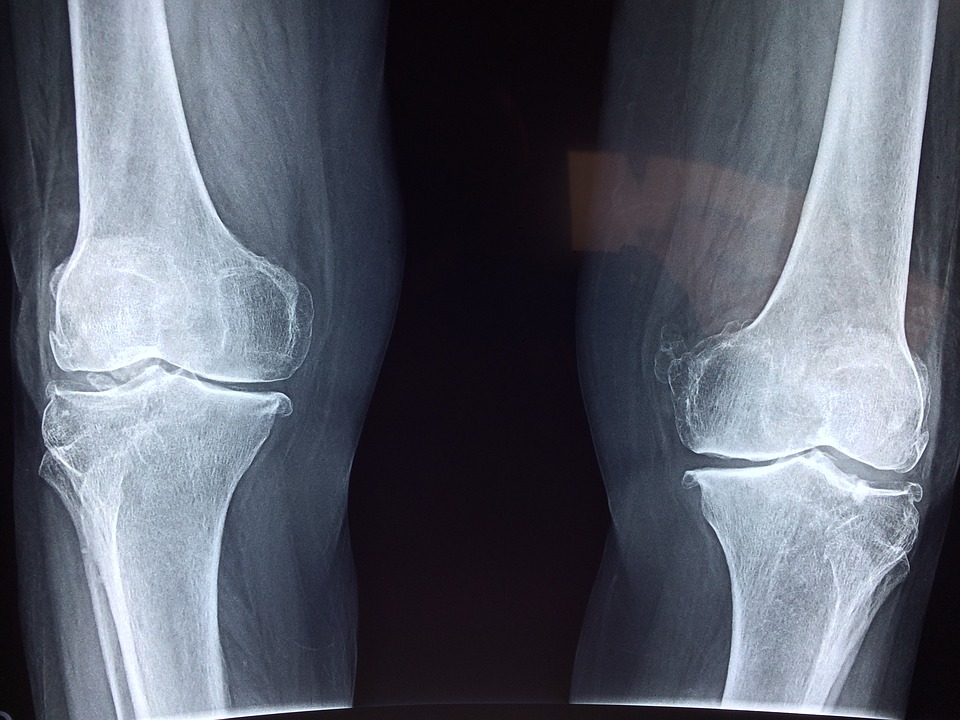

1.変形性股関節症

変形性股関節症とは?どんな手術?手術のあとの何がだめ?

術後気をつけること、観察・記録のポイントも!

4.変形性膝関節症

変形性膝関節症とは?何のための手術なの??

術前のここがキーポイントだった!!